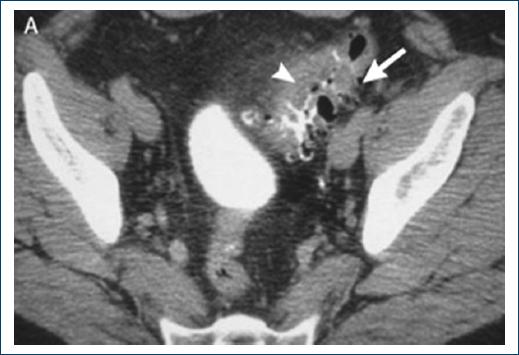

This is a 57-year-old male patient with no pathological history relevant to the case, who began his condition 8 h before going to the hospital with pain in the left iliac fossa as well as little tolerance to oral administration. On arrival, laboratories and CT scans are obtained, reporting Hinchey IIA diverticulitis, for which he is treated with conservative management based on antibiotics, to which the patient shows unfavorable evolution. In a second tomography study, the diagnosis of intestinal obstruction secondary to an acute diverticular inflammatory process was made (Fig. 1). The obstructive process did not progress favorably for 24 h, so it was decided to operate on the patient. In this case, a laparoscopic approach is chosen.

Figure 1 Axial cut of abdominal tomography with oral contrast at the level of the pelvis. Multiple saccular defects are observed at the level of sigmoid colon associated with mural thickening and edema of adjacent mesenteric fat. Findings consistent with diverticulitis.